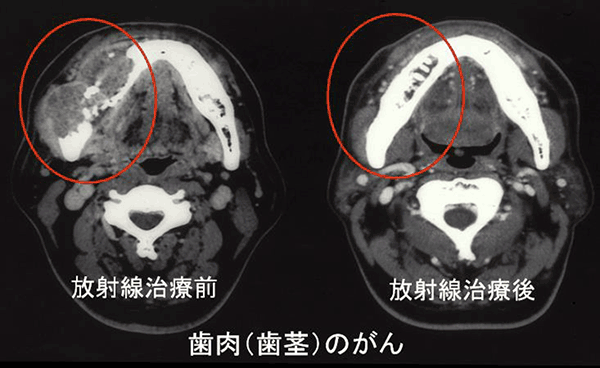

放射線治療は、手術療法・化学療法と並んでがん治療の三本柱の1つです。局所療法としての手術と比較したときの放射線治療の特徴は、「切らずに根治をめざす」ことであり、多くの場合「怖くない、痛くない、臓器の形態と機能を温存できる」治療です。症例によっては、臓器温存だけでなく、本来生体の持っている復元力によって「損傷していた臓器の修復」が達成される場合もあります(図1)。この特徴は、「腫瘍に精密に照射線量を集中させ,周囲の正常組織への線量を極力低減させる」ことによって達成することができ、近年の機械情報工学のめざましい発展によって大きく進歩しています。早期がんでは放射線治療単独でもがんを根治させることが出来ますが、進行がんに対しては手術や化学療法と力を合わせて治療に当たります(これを集学的治療と呼びます)。また、根治的治療の一方で、症状を軽くするための緩和的な目的にも大変大きな効果を示します。緩和治療としては薬物療法が一般的ですが、さまざまな副作用を伴います。放射線治療は症状を軽減する程度の照射線量であれば多くの場合ほとんど副作用を伴わず、また腫瘍の進行を抑えることによって延命効果も期待されます。もう一つ、放射線治療の大きな特徴は、「全身を診る」ことです。がんは全身に多発したり、複数の異なるがんを同時に持ったりすることもありますので、全身を診ることの出来る放射線治療医は患者さんの状態や治療目的に応じたバランスのとれた判断が可能です。放射線治療医は、「切らずに優しく治せる」特徴を最大限に活かし、がん患者さんの気持ちに寄り添いながら患者さんとともに治療法を考えていく ことをモットーにしています。

放射線治療によりがん病巣が消失しただけでなく損傷していた下顎骨が元通りに修復され ています。